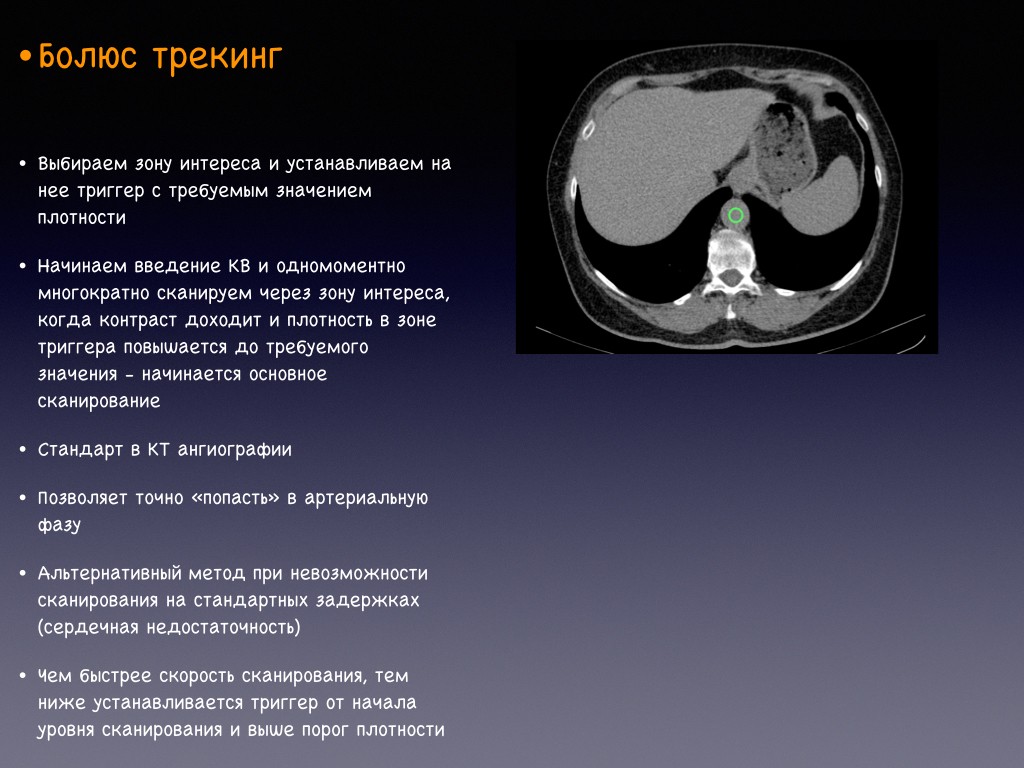

Фотографии и снимки КТ легких без контрастных веществ

Раздел: Визуальный дайджест